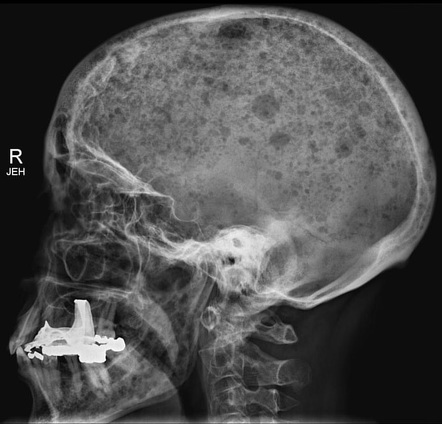

Q.54. A young man comes with headache, he is describing that this headache is the worst headache in his life. Which of the following will be less helpful?

Correct Answer : C

Skull X-ray, as it's not sensitive for causes like subarachnoid hemorrhage.